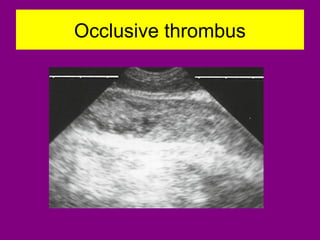

Occlusive thrombus